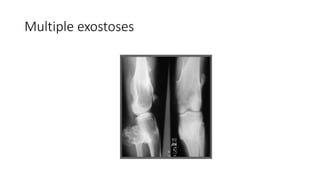

Multiple exostoses

METAPHYSEAL STRIATIONS BONY ISLANDS